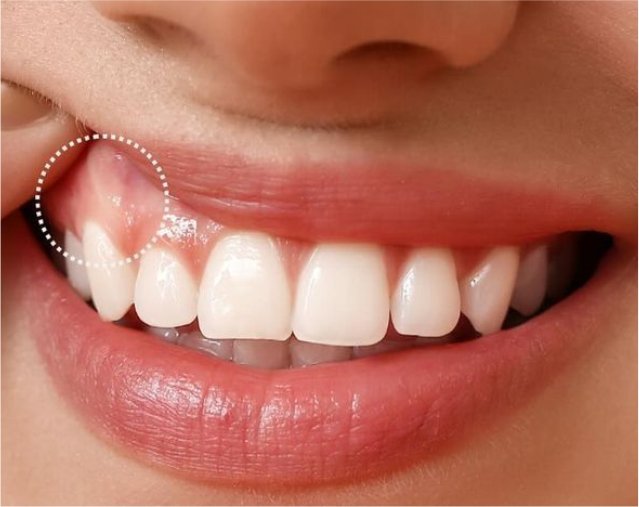

Periodoncia

La salud de las encías es fundamental para la estabilidad de los dientes e implantes.